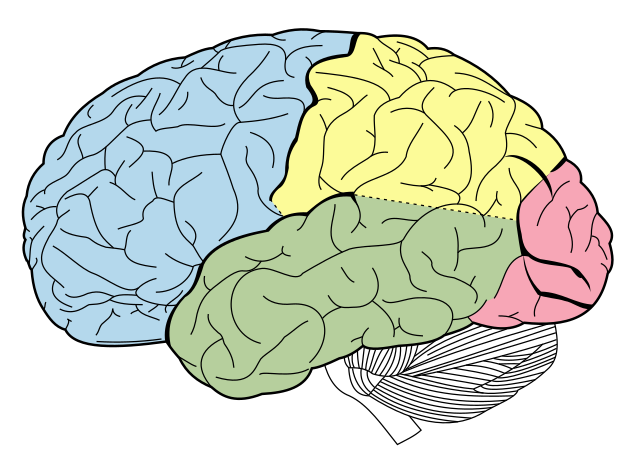

Los investigadores sugieren que, al estimular determinadas funciones cognitivas, se activan también circuitos neuronales implicados en la ejecución motora. “No significa que el ejercicio físico deje de ser importante, sino que puede complementarse con intervenciones cognitivas específicas para potenciar sus efectos”, aclararon los especialistas.